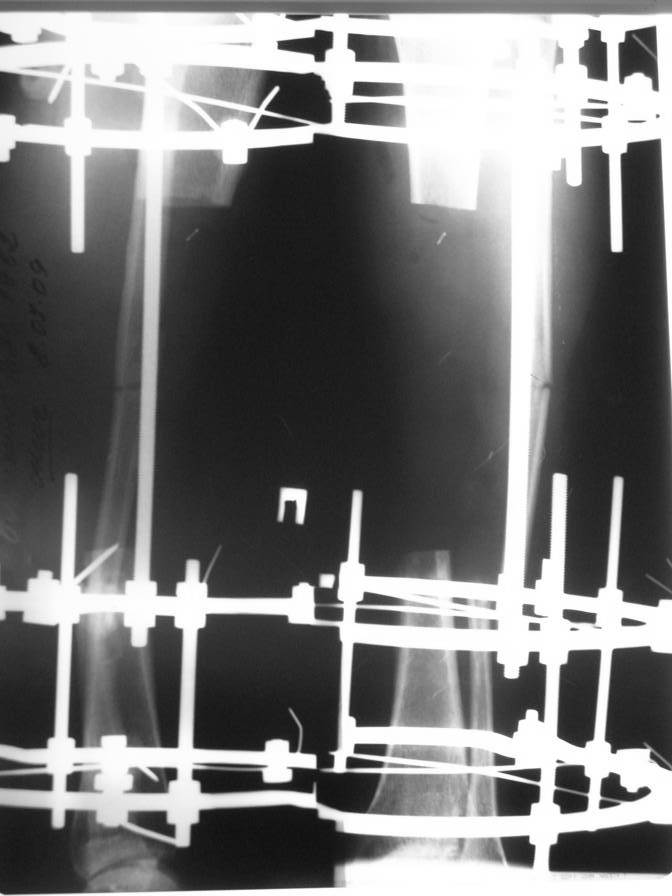

ВОЗМОЖНО В ТАКИХ СЛУЧАЯХ БИОС С ПОСЛЕДУЮЩИМ ТРАНСПОРТОМ РЕГЕНЕРАТА. КОМПОНОВКУ АППВРАТА МОЖНО ИСПОЛЬЗОВАТЬ ТАКУЮ (ФОТО ИЗ КЛИНИКИ ПРОФ. ФРИДРИХА - БРЕМЕН)